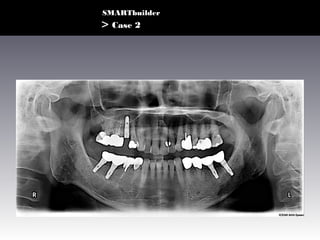

> Case 2

• UJS (M/64)

• #4 Extraction d/t Crown Fx. ( 2 months ago)